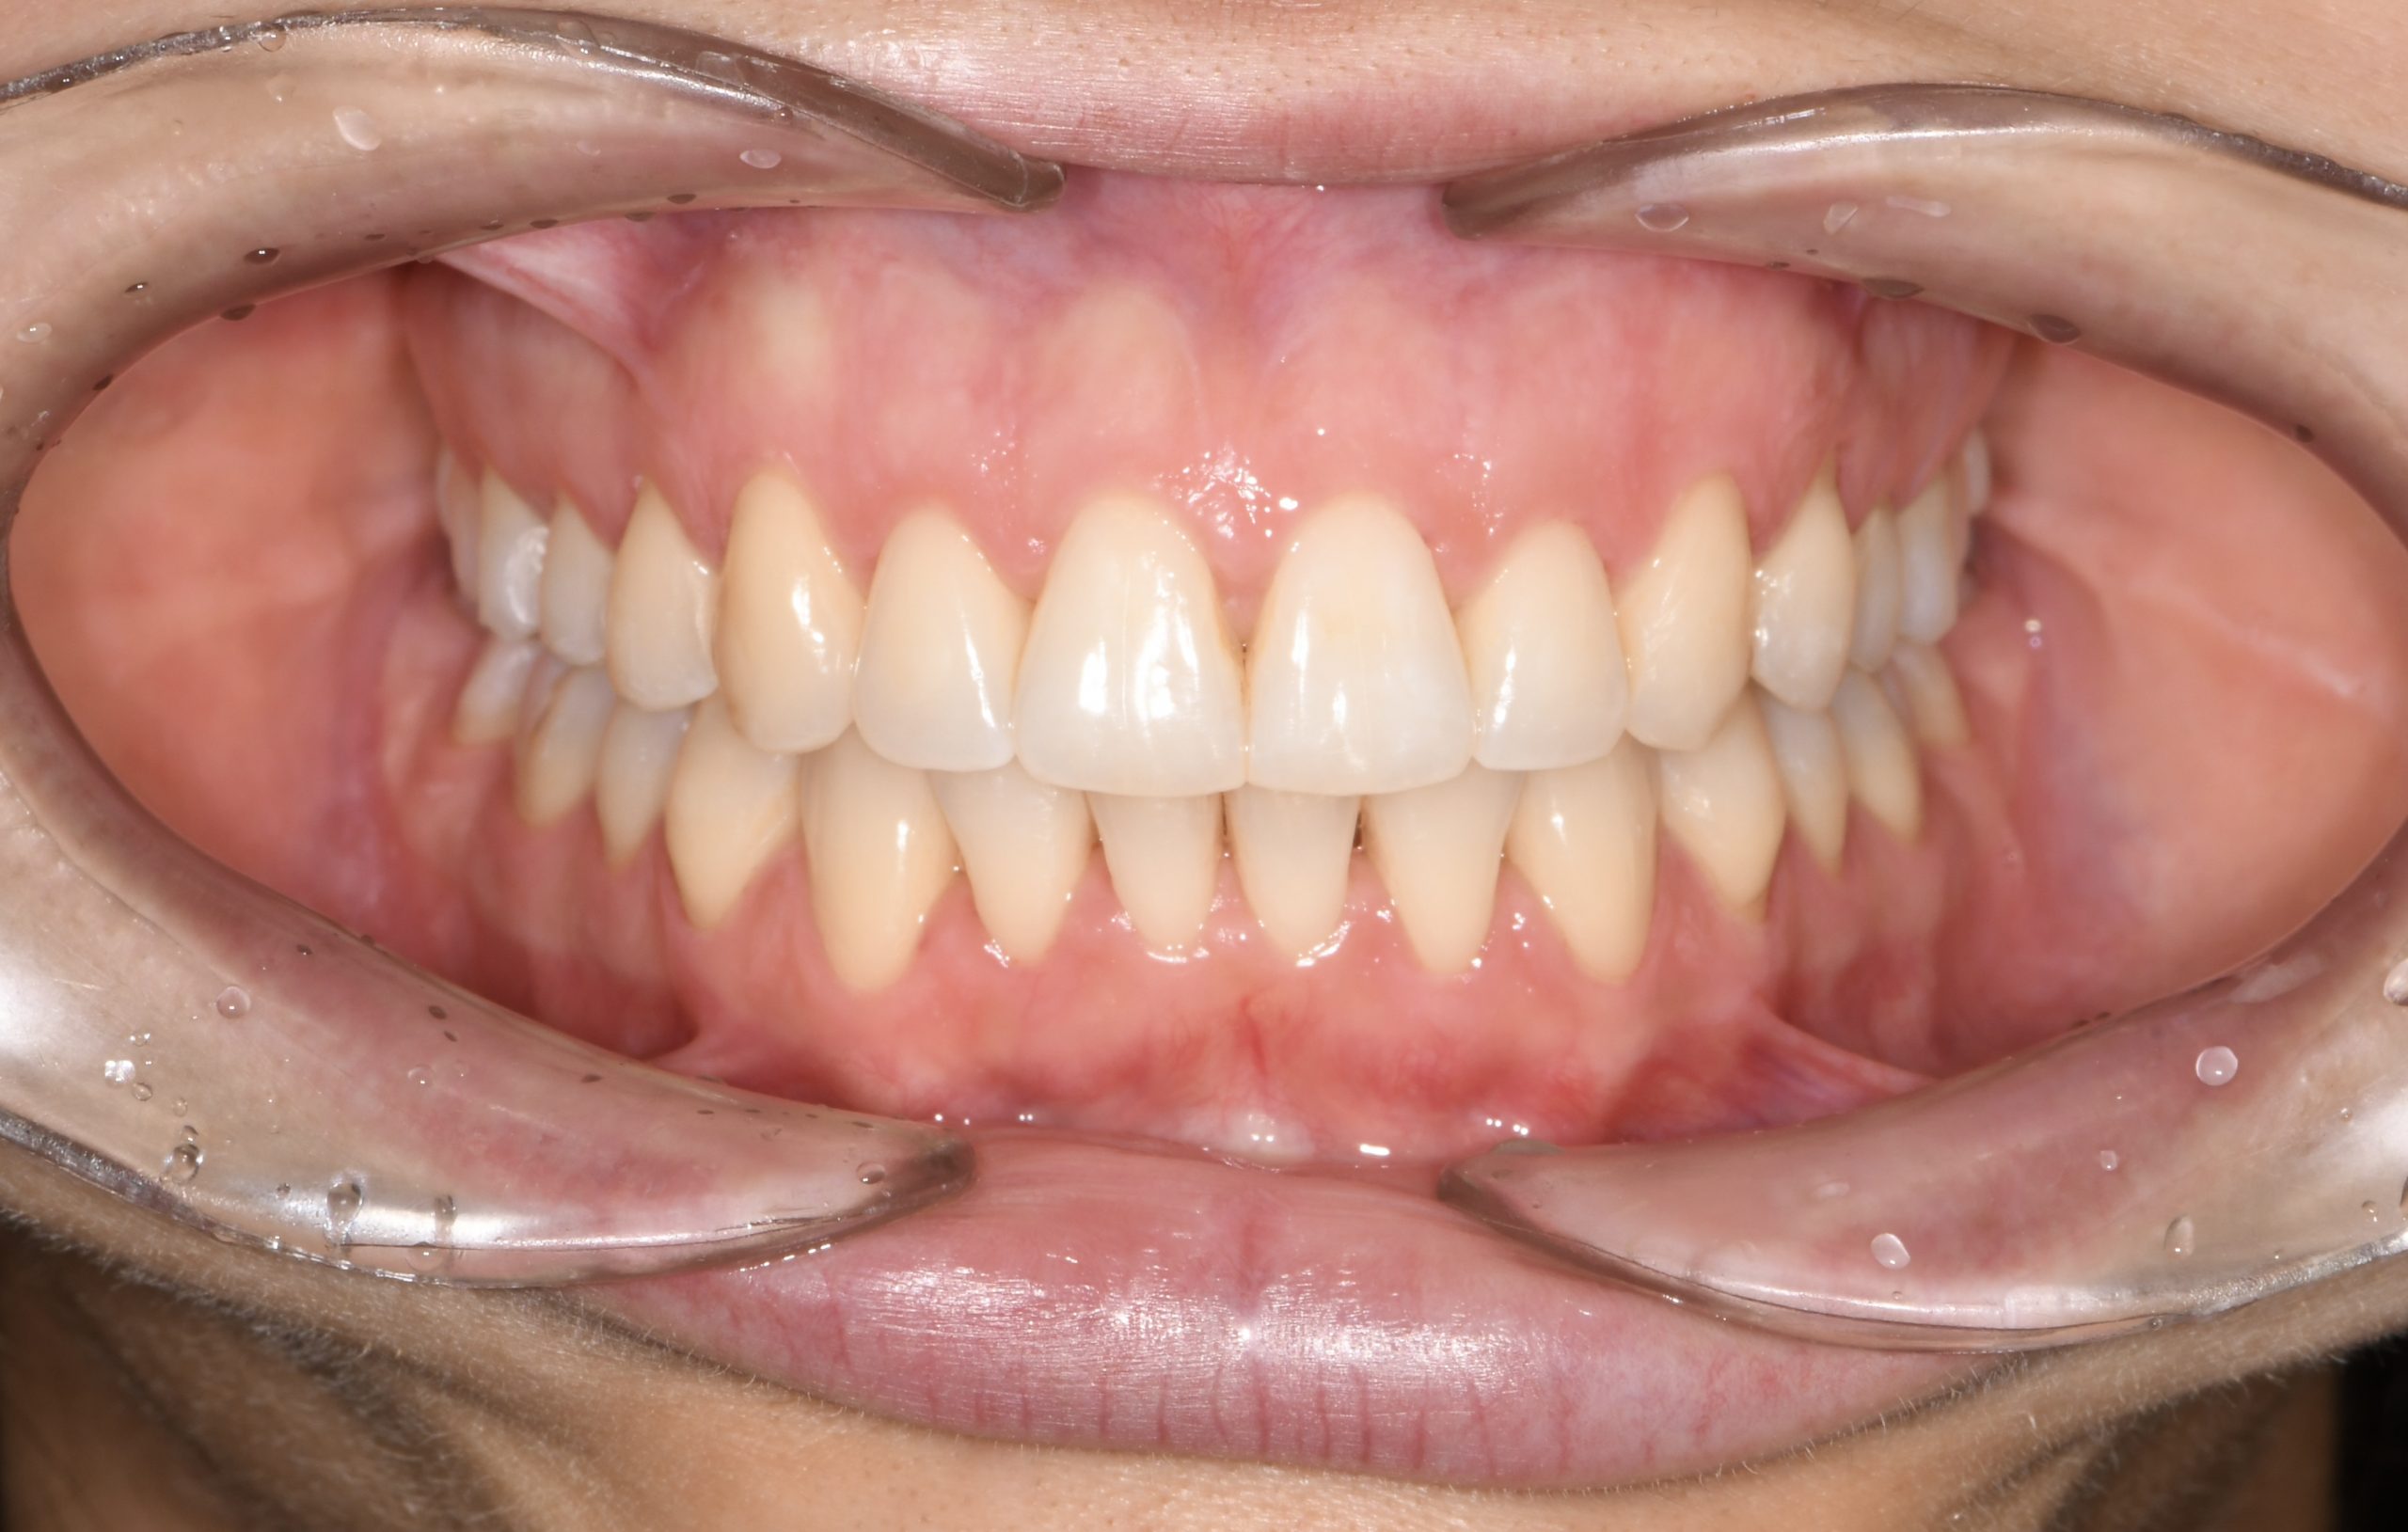

Az elmúlt évekből rengeteg szakmai referenciát tudnánk bemutatni, amelyek különböző fogszabályozási problémákat oldottak meg. Válogatva a több száz esetből, ezen az oldalon olyan képeket, információkat igyekeztünk bemutatni, amelyeknek a segítségével a jövőbeni pácienseinknek azt tudjuk üzenni: A Te fogsorod is lehet gyönyörű!

(Képeket a Pácienseink külön írásos beleegyezésével mutatjuk be!)